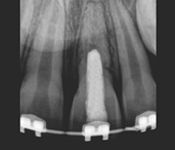

Pictured: Root Fractures/Splinting of Teeth and 1 Year Recall with Complete Root Formation

Parent of our 7-year-old patient was distraught by an injury that indicated horizontal root fractures in tooth #8 and tooth #9. Treatment involved splinting of teeth. After 1 year recall , the patient successfully had complete root formation.